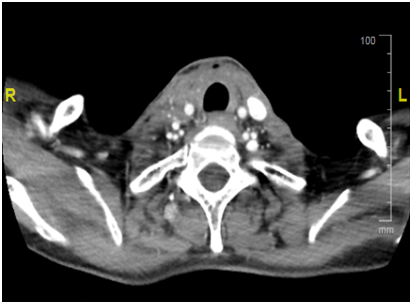

Figure 1 a) Response after Lenvatinib.

b) Disease prior to Treatment with Lenvatinib.

Our patient is a 55yrs. old female with long standing history of Goitre. She underwent total thyroidectomy after confirming Papillary Thyroid cancer on FNA at presentation with slowly progressing neck mass over a course of 1yr. Initial TNM stage showed a T3 N1 M0 Papillary thyroid tumour with extra capsular extension. She proceeded to have radio iodine ablation in May 2016 with 5000Mbq which showed uptake in thyroid bed and Rt neck nodes at level 2. She was then maintained on TSH suppressive dose of thyroxine. Unfortunately, she suffered a relapse in the neck with neck nodes 3 months later i.e. in august 2016 and proceeded to have neck clearance. Again nodes in the RT neck were noted along with extra capsular extension. Pathology, however, showed anaplastic thyroid cancer. Within 6 weeks from her second surgery she came back with rapidly progressing bilateral lower neck nodes. She had a CT which confirmed the recurrence with no distal metastasis. Her recurrence, now second after initial surgery, was deemed inoperable due to the tumour being wrapped around the carotid artery. She proceeded with External Beam Radiotherapy for local control. She progressed on radiotherapy within 2weeks of the start of treatment. This was confirmed on repeat CT scan. No distal metastasis was detectable. Unsurprisingly patient’s thyroglobulin levels were never very high (max level of 20.6). Subsequent levels were within normal limits with no detectable Anti Thyroglobulin Antibody. At this point patient was started on 24mg of Lenvatinib. On her next follow up after 2weeks patient had a complete clinical resolution of her neck nodes and a subcutaneous suprasternal mass as seen previously showed considerable shrinkage. Patient remained troubled with grade 2 fatigue and anorexia but nothing else. At her next appointmentafter2 weeks she had complete disappearance of her disease so much so that a crater was left in suprasternal area i.e. site of her previous subcutaneous tumour extension. Due to persistent fatigue and anorexia dose of Lenvatinib was reduced to 14mg which she is tolerating well. She had a CT at 6weeks which confirmed complete resolution of her disease and no metastasis. She has recently undergone debridement of the lower anterior neck wound and no disease has been detected on biopsy. She awaits her next staging CT in near future (Figure 1).